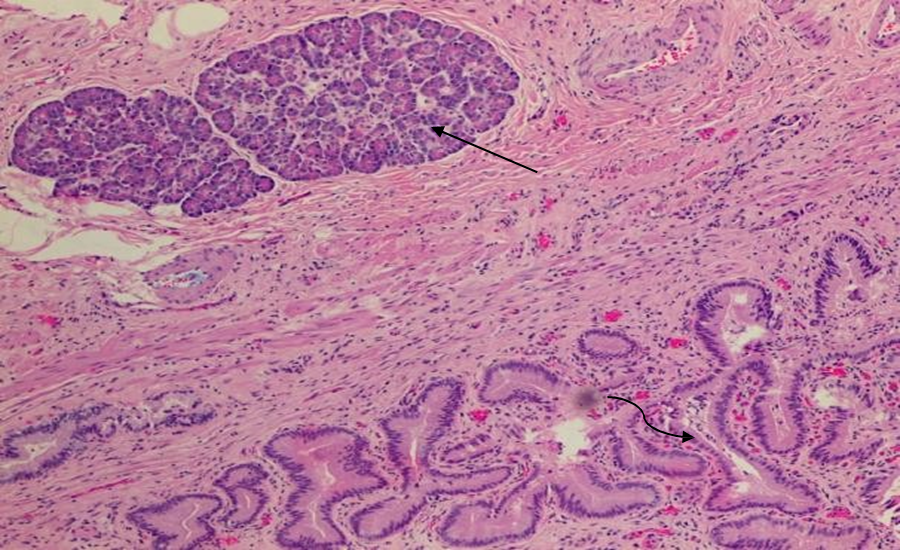

Figure 2 Histopathology of pancreatic heterotopia in the gallbladder of a 51-year-old woman using a hematoxylin and eosin stain demonstrates mucin secreting columnar epithelium lining the cystic duct (curved arrow) and pancreatic tissue (straight arrow). [100x view]